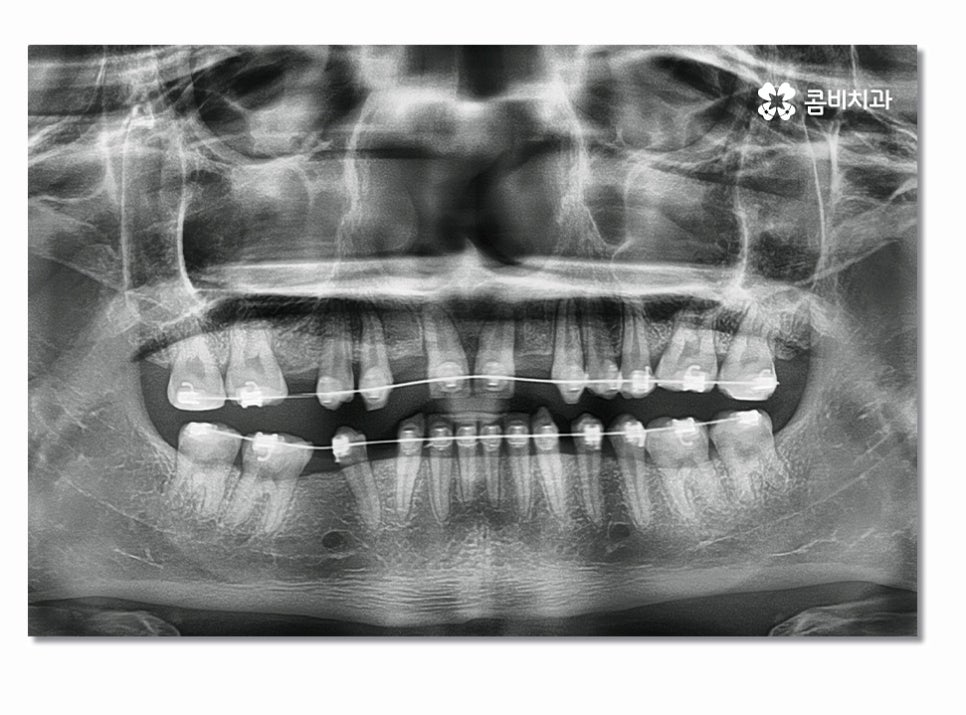

치아교정은 심미적인 개선을 위해서 치료를 받기도 하지만

치아의 건강을 위해서도 치료 목적을 두고 있는데요.

우리가 평생 자연치아를 건강하게 지켜야 한다는 관점으로 볼 때

불규칙한 치열과 부정교합은 빠르게 치료를 하는 편이

심미적인 개선뿐 아니라 치아 건강에도 중요할 수 있어요.

특히 위 환자분의 경우에는 앞니 올 세라믹 치료와

치아교정, 임플란트를 동시에 진행해야 했기 때문에

전체적인 조화와 치료 계획을 철저하게 세울 필요가 있었고